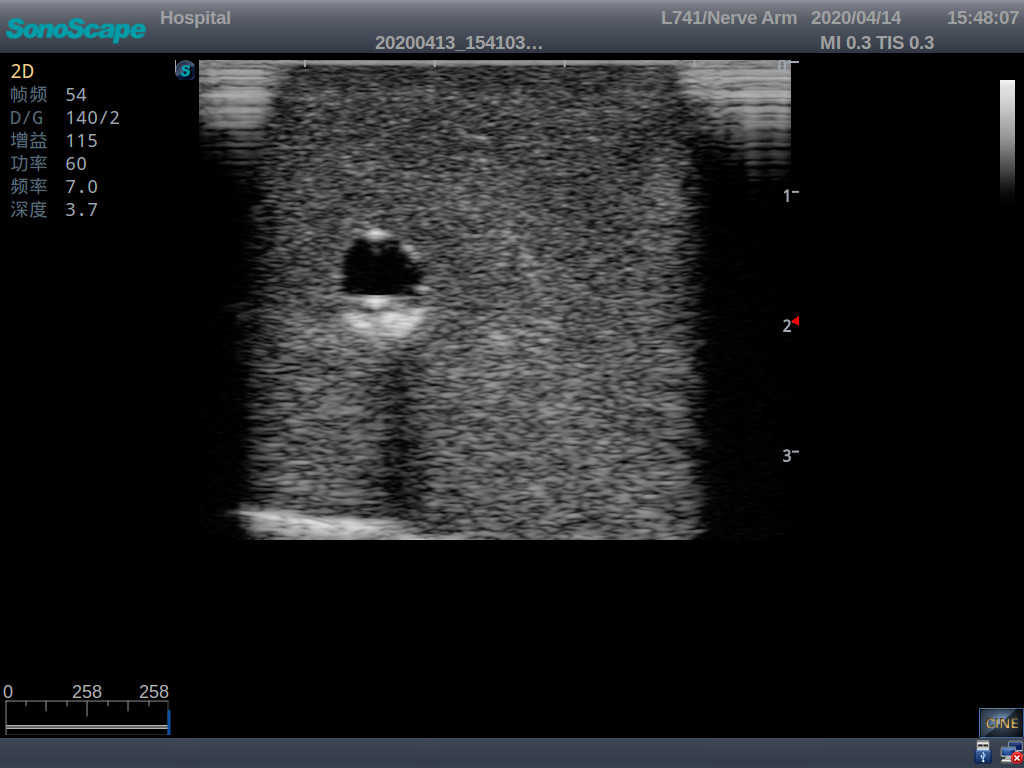

Model TYE1510.1

Outline

It is a model covering up from lobulus auriculae plane to the umbilical plane, and it has anatomical structures like clavicle, rib, sternocleidomastoid, jugular vein and basilic vein.

1)   Made of high molecular polymer ultrasound material, close to the real skin

2)   It can be used by real ultrasound machines

3)   Clear and real images of the tissues and organs (basilic vein and superior vena cava)